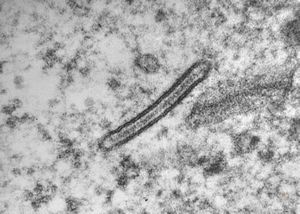

M,7m. | Birbeck granules (Langerhans granules, X-granules) - skin, histiocytosis X

M,7m. | Birbeck granules (Langerhans granules, X-granules) - skin, histiocytosis X